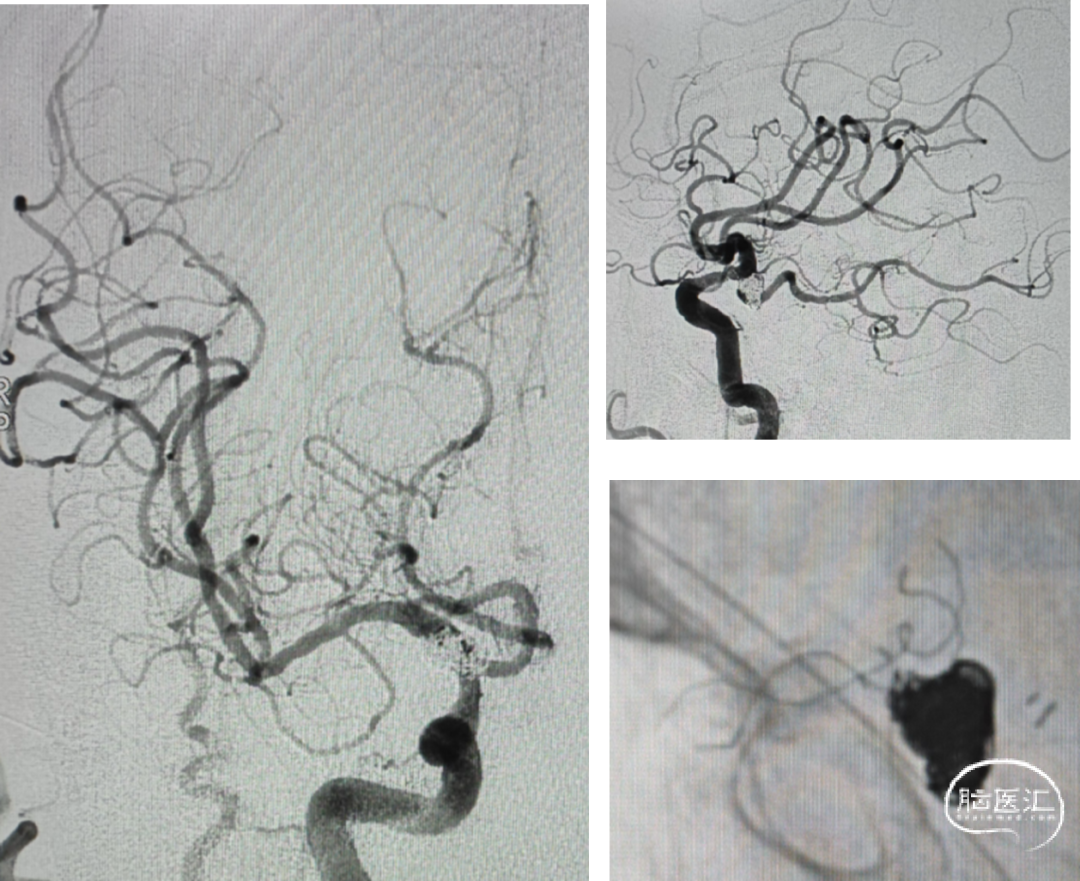

支架选择

LEO3.5x25 Atlas 3.0x15

工作位

echelon10(45)J-7(90右偏90)-15(90);echelon10(90)J-5(45右偏90)-15(90)

Axium3d620;axium3d15

管2:target3d24